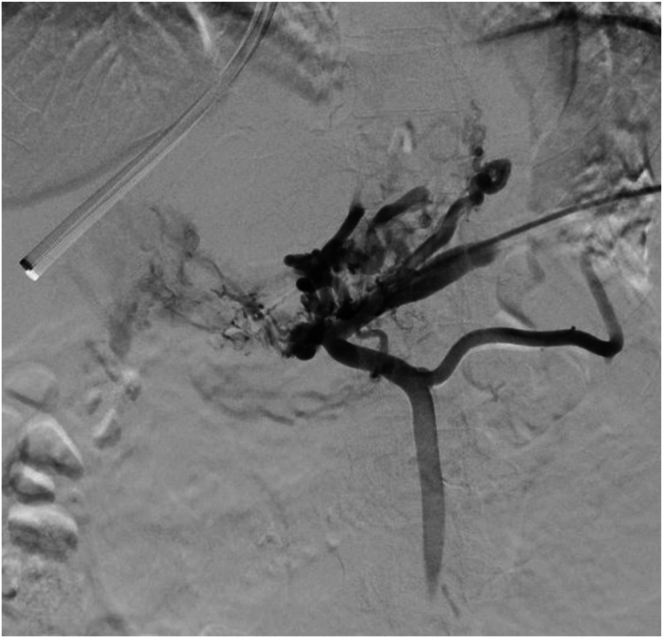

门静脉再通经颈静脉肝内门静脉系统分流术(pvrtips)是一种安全有效的门静脉高压症(PH)减压手术。在这个简短的病例系列中,2名患有慢性非肝硬化门静脉血栓的女性接受了PVR-TIPS治疗。两个病人都希望怀孕。如果不治疗她们的PH值,她们的怀孕会造成危及生命的静脉曲张出血的重大风险。两名患者对手术耐受良好,分娩时没有出现PH并发症。在未来希望怀孕的非肝硬化门静脉血栓患者中,PVR-TIPS应被考虑作为PH的最终治疗。

Portal vein recanalization transjugular intrahepatic portosystemic shunt (PVR-TIPS) is a safe and effective procedure for decompression of portal hypertension (PH). In this short case series, 2 women with chronic noncirrhotic portal vein thrombosis were treated with PVR-TIPS. Both patients hoped to conceive. Without treatment for their PH, their pregnancies posed a significant risk of life-threatening variceal bleeding. Both patients tolerated the procedure well and delivered without complications of PH. In future cases of noncirrhotic portal vein thrombosis in patients hoping to conceive, PVR-TIPS should be considered for definitive treatment of PH.